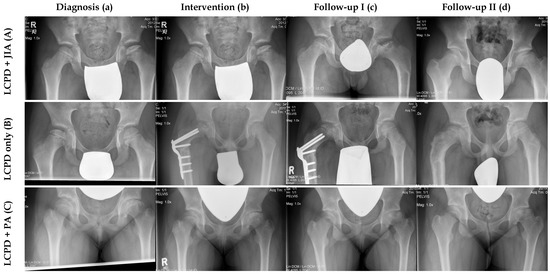

| Patient Number | Type of JIA | Sex | Age at Onset LCPD (y) | Age at Onset JIA (y) | Lateral Pillar Classification | Stulberg Classification | mHHS (p) | Treatment | Follow-Up Time (y) |

|---|---|---|---|---|---|---|---|---|---|

| 1 | Oligoarticular | m | 7.1 | 7.0 | C | II | 87 | Arthrography, proximal femoral varus osteotomy, Salter osteotomy | 11.1 |

| 2 | Enthesitis-related arthritis | m | 9.1 | 9.2 | - | III | 100 | Permanent trochanteric epiphysiodesis | 12.4 |

| 3 | Oligoarticular | m | 14.7 | 14.6 | B | III | 76 | Distraction frame, retrograde drilling, open waisting of femoral neck, open arthrolysis and partial arthroscopic synovialectomy | 10.5 |

| 4 | Oligoarticular | m | 5.0 | 4.6 | C | II | 65 | Arthrography, proximal femoral varus osteotomy, permanent trochanteric epiphysiodesis | 3.4 |

| 5 | Enthesitis-related arthritis | m | 3.0 | 11.5 | C | I | 98 | Proximal femoral varus osteotomy | 18.3 |

| 6 | Oligoarticular | m | 8.7 | 8.8 | B | II | 95 | Arthrography, proximal femoral varus osteotomy | 7.9 |

| 7 | Oligoarticular | m | 5.2 | 5.2 | B | I | 96 | Nonoperative treatment | 6.8 |

| 8 | Psoriatic arthritis | f | 11.8 | 12.0 | C | V | 57 | Hip joint puncture, retrograde drilling | 2.8 |